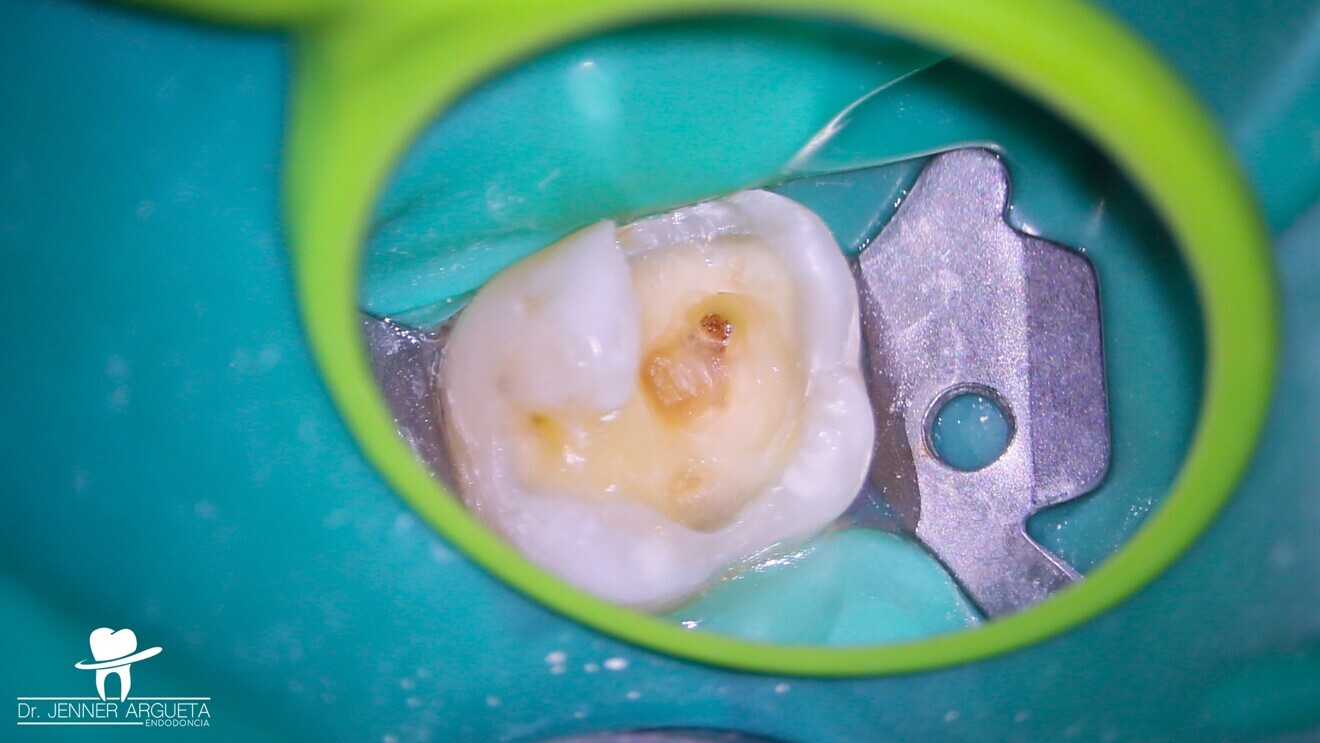

Fig. 2: Bitewing radiograph showing evidence of a deep restoration in tooth #16 at mesial level. Under-mineralised tissue was found close to the mesial pulp horn.

The patient attended reporting short-term pain in tooth #16 (Fig. 1). Through radiography, clinical assessment and an analysis of the patient’s clinical history, reversible pulpitis was diagnosed, and a deep Class II temporary restoration was found (Fig. 2).